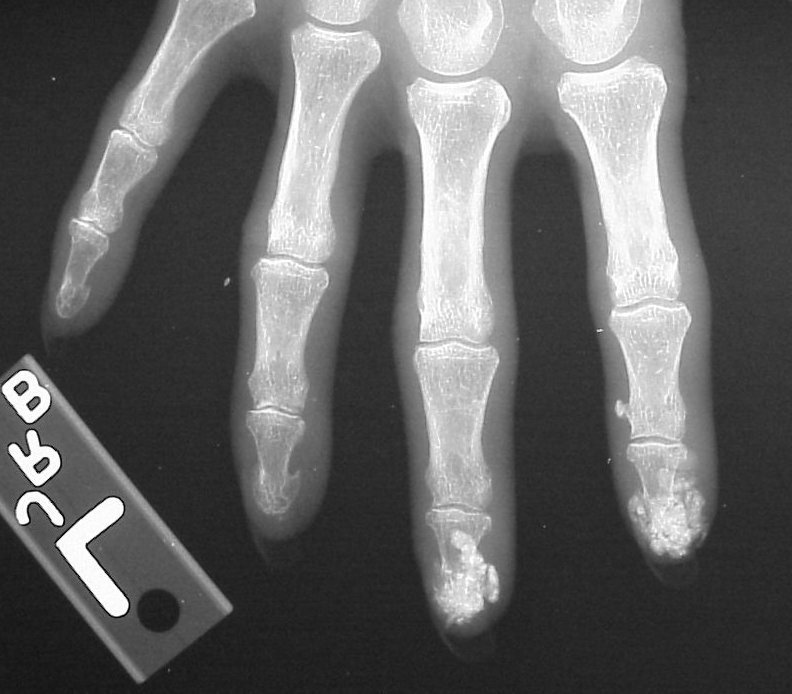

Xrays show extensive soft tissue calcifications of the distal pulp of these fingers.

Soft tissue calcifications are typically diffuse, and can not be simply "shelled out". Thorough excision may lead to extensive skin loss, and partial removal (limited incision and drainage) may be a reasonable compromise approach in selected cases.